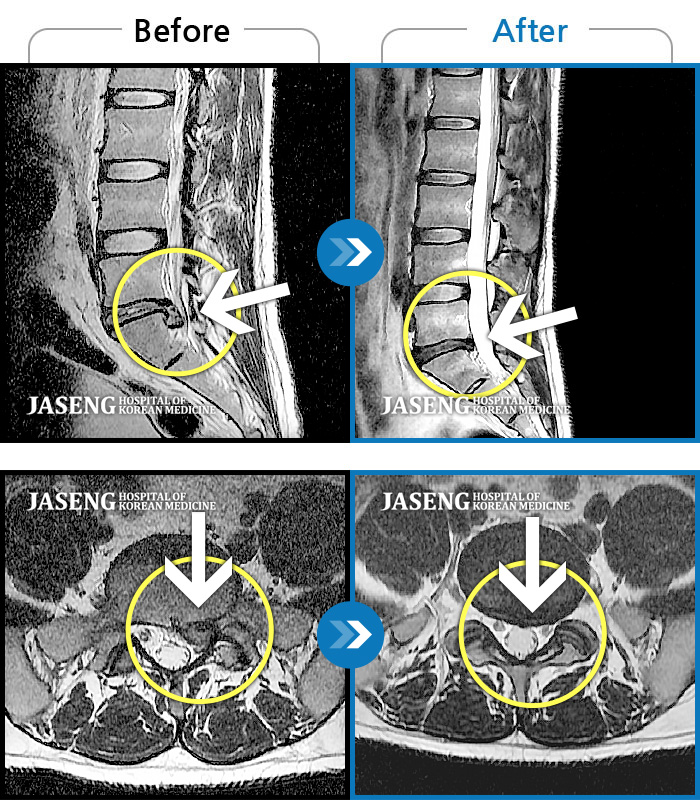

MRI 치료사례

요부 통증 및 좌측 하지 통증이 심해서 걸을 수가 없다.